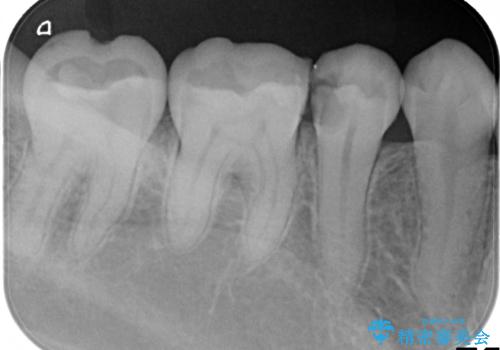

- 歯が欠けて、そこに食べ物が詰まるとのことで来院されました。

虫歯が大きく進行していました。

顕微鏡下で丁寧に虫歯を取り除き、セラミックインレーによる修復治療を行いました。